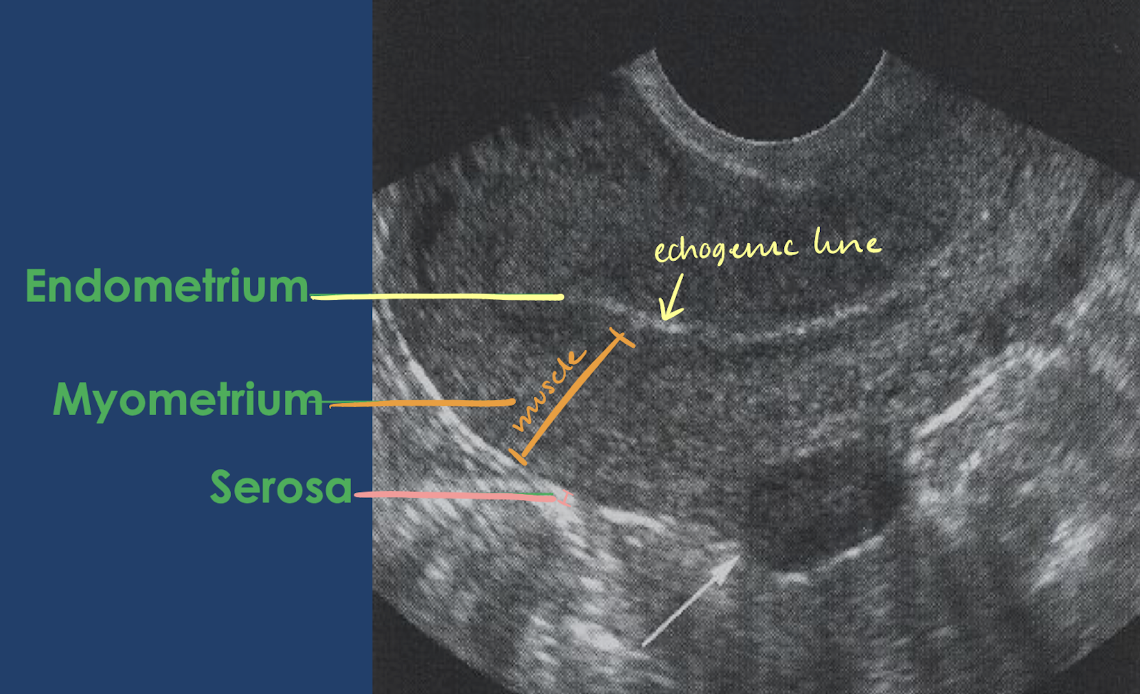

3 tissue layers of the uterus

perimetrium (serosa)

myometrium

endometrium

thin, external layer

echogenic

middle, thickest layer

hypoechoic

made up of smooth muscle

innermost layer

thickness and appearance depends on menstruation cycle

echogenic-mildly hypoechoic